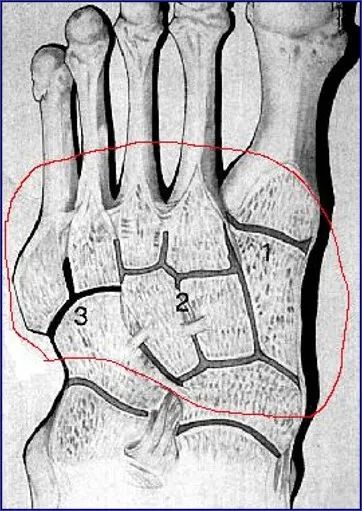

整个关节结构可以划分为三个柱:

• 内侧柱:第一跖骨和内侧楔骨

• 中柱:第2、3跖骨和中外侧楔骨

• 外侧柱:第4、5跖骨和骰骨

第二跖骨基底部深入到3个楔骨形成的马蹄形凹槽中,在跖跗关节的稳定性中起重要作用。

跖骨的基底及楔骨、骰骨形成一拱形结构,也有较好的稳定作用。